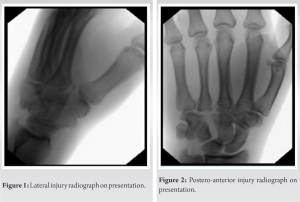

A 26-year-old right-hand dominant Caucasian male without significant medical history landed on his outstretched left hand when crashing his all-terrain vehicle, resulting in immediate pain and swelling. An outside urgent care center found no fractures or dislocations on plain radiographs and subsequently splinted the left wrist due to pain. He presented to an orthopedic hand surgery outpatient office 4 weeks after the injury with persistent pain and decreased range of motion. No obvious deformity was noted, but the patient was tender to palpation over the dorsal carpus as well as the carpal tunnel. The patient was neurovascularly intact at the time of presentation. New plain radiographs were obtained, demonstrating an isolated dorsal hamate dislocation in the absence of any fracture, as noted in Fig. 1 and 2. Given the chronicity of the injury, closed reduction was not attempted due to the high likelihood of failure. The patient underwent an open reduction with internal fixation of the isolated hamate dislocation.